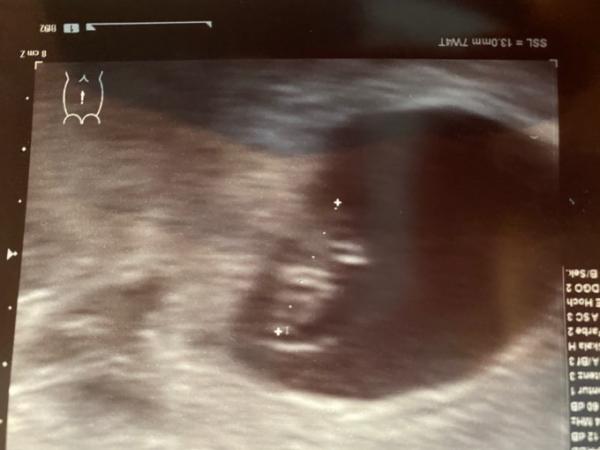

Nach 1 Stunde Wartezeit war ich dann dran! Erst hat er gar nichts gefunden im vaginalen Ultraschall! Aber er ist ganz cool und locker geblieben! Er machte Ultraschall an Bauch und Zack zeigte sich der kleine Bewohner! Er hat es sich tief in meiner Gebärmutter gemütlich gemacht! Das Herz wummerte wie verrückt und es ist genauso groß wie es sein muss! ich bin verliebt Habe meinen Mutterpass bekommen! Das Bild ist eher schlecht als recht, aber egal! Ich bekomme das Ultraschall Video immer auf cd mit, das gucke ich heute bestimmt noch 100 mal an ! Ich drücke allen die heute noch dran sind die Daumen !!!

Bild zu FA Termin - Forum für Juli - Mamis